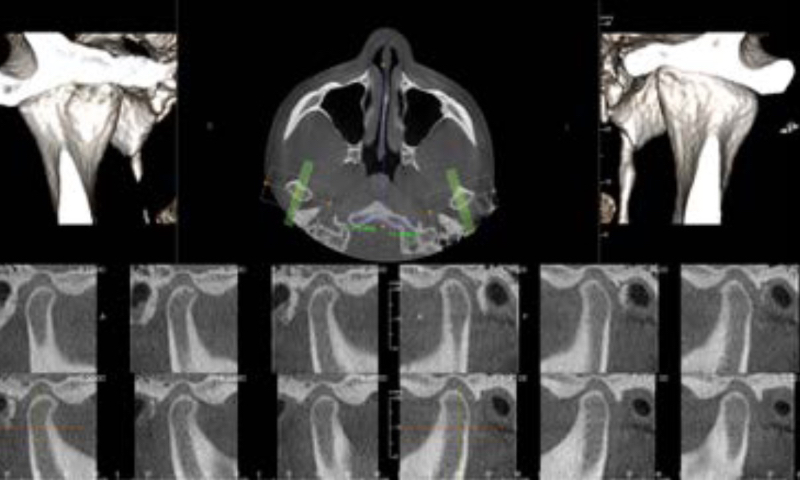

全周囲からの情報を得られる360°スキャニング

全周囲からの情報を得るために 360度回転して撮影します。撮影中の回転角度を大きくすると、情報量が多くなり、画像データが補正できます。

パノラマ撮影機をベースにしたCT撮影機は、その構造上200度前後の回転しかできない機種が多く、メタルアーチファクトを抑えることができません。![]()

360°スキャンで金属アーチファクトの発生が少ない。